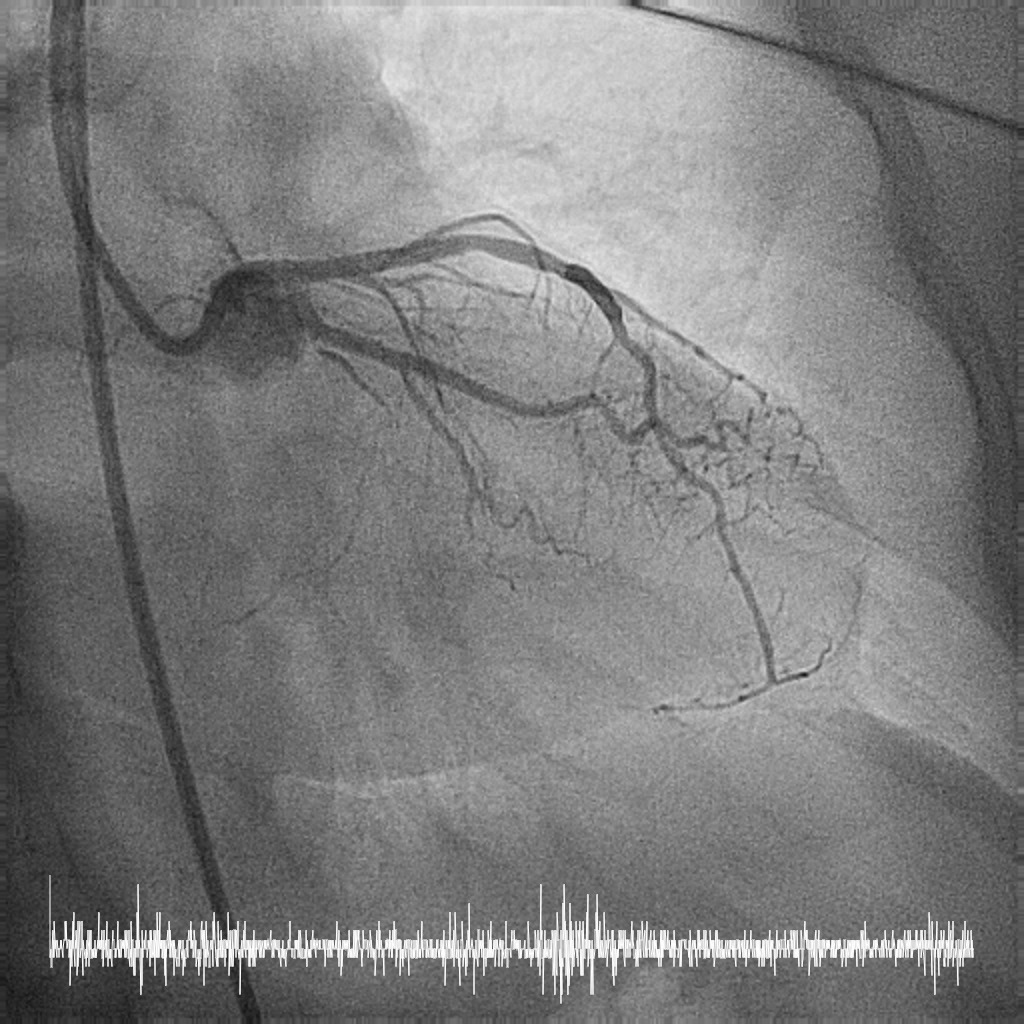

Relevant Catheterization Findings

Coronary angiography performed via right radial approach with a 5F Optitorque diagnostic catheter.

LMS: Ostia LMS 99% stenosis with pressure dampingLAD: Proximal LAD 30-40% stenosisLCx: NormalRCA: Dominant. Normal.

Patient developed short run VT during engagement to left main.

LMS: Ostia LMS 99% stenosis with pressure dampingLAD: Proximal LAD 30-40% stenosisLCx: NormalRCA: Dominant. Normal.

Patient developed short run VT during engagement to left main.

Femoral approach was chosen with a 7F sheath. A 7F JL4 guiding catheter was used for better support. JL4 was not coaxially engaged but positioned close to the ostial LM. Sion Blue ES was wired into LAD from the aortic cusp. A BMW wire was wired into LCx to provide additional support and as a safety wire in case of plaque shift into ostial LCx. Ostial LM was predilated with 3.0/10mm NC balloon at 12ATM which was delivered via Sion Blue ES with the guide and wire floating in the aorta. IVUS after predilatation revealed an ostial LM MLA 5.28mm2 with vessel size 4.0mm. Proximal LAD measured 3.0mm in size and exhibited fibrotic plaque with 70% plaque burden. Both ostial LM and proximal LAD were predilated with 3.0/15mm NC balloon delivered using the floating guide and Sion Blue ES. A 3.0/33mm DES was delivered and deployed with similar technique into proximal LAD using multiple projections for precise positioning to ensure proximal stent edge protrusion of 1-2mm into the aorta. POT of LM and ostial flare were performed using 3.75/15mm NC balloon. Proximal LAD was postdilated with 3.0/15mm NC balloon. IVUS confirmed a well-opposed stent without stent edge dissection. The final ostial LM MSA was 9.7mm2, with stent protrusion (1.7mm) into the aorta (less than one quadrant). The entire ostial LM was covered with stent struts.